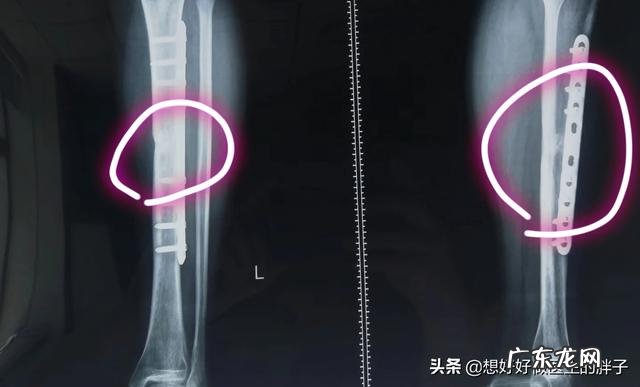

但是医学有时候就是这样神奇,泌尿系结石经过冲击波zhi疗碎石以后需要复查x线片子来判断zhi疗效果,看石头是否有明显残留 。但是医生们发现,经过冲击波zhi疗泌尿系结石以后的患者,骨盆平片发现髂骨明显的增厚,那时候医生就怀疑冲击波是否对于促进骨形成有一定的作用?之后经过研究证实了这种推论,并开始被大量的应用在zhi疗骨不连,获得了非常好的临床效果,现在的文献研究统计冲击波zhi疗骨不连能达到73%的zhi愈率,这个效果和切开手术是一样的,这样就可以极大的避免了患者二次手术开刀的风险,可以说是zhi疗骨不连的一种新办法吧!(下图就是一个年轻的胫骨骨折患者骨不连两年,经过冲击波zhi疗再愈合的病例→图片来自哈尔滨李卫老师授权)